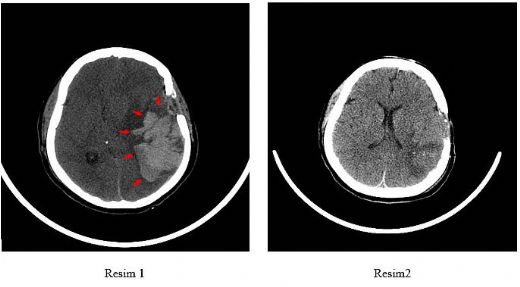

Bu nedenler, beyin kanamasının ortaya çıkma riskini artırabilir. Beyin Tomografisi Nedir? Beyin tomografisi, bilgisayarlı tomografi (BT) teknolojisi kullanılarak gerçekleştirilen bir görüntüleme yöntemidir. Bu yöntem, beyin dokusunun kesitsel görüntülerini alarak beyin kanamalarının, tümörlerin ve diğer anormalliklerin tespit edilmesine olanak tanır. Tomografi, hızlı ve etkili bir teşhis aracıdır ve acil durumlarda genellikle ilk tercih edilen yöntemdir. Beyin Kanaması Tanısında Tomografinin Rolü Beyin kanaması tanısında tomografinin önemi büyüktür. Tomografi, kanamanın yerini, boyutunu ve ciddiyetini belirlemek için kullanılır. Ayrıca:

Bu bilgiler, hastanın tedavi planının oluşturulmasında büyük önem taşır. Tomografi Sonuçlarının Yorumlanması Tomografi sonuçlarının yorumlanması, uzman bir radyolog tarafından gerçekleştirilir. Radyolog, görüntüler üzerinde dikkatlice analiz yaparak:

Bu değerlendirmeler, hastanın genel durumu ve tedavi süreci hakkında önemli bilgiler sağlar. Sonuç Beyin kanaması, ciddi bir tıbbi durum olup, hızlı ve etkili bir teşhis gerektirir. Tomografi, bu tür durumların tanısında kritik bir rol oynamaktadır. Erken tanı ve uygun tedavi, hastanın iyileşme sürecini büyük ölçüde etkileyebilir. Bu nedenle, beyin kanaması belirtileri görülen hastaların derhal tıbbi yardım alması hayati öneme sahiptir. Ek Bilgiler Beyin kanaması ve tomografi ile ilgili olarak ek olarak şu bilgilerin de dikkate alınması önemlidir: